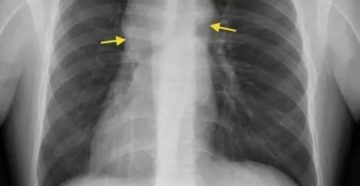

Как выявить метастазы в легких. КТ и рентгенологические признаки Компьютерная томография — один из самых…